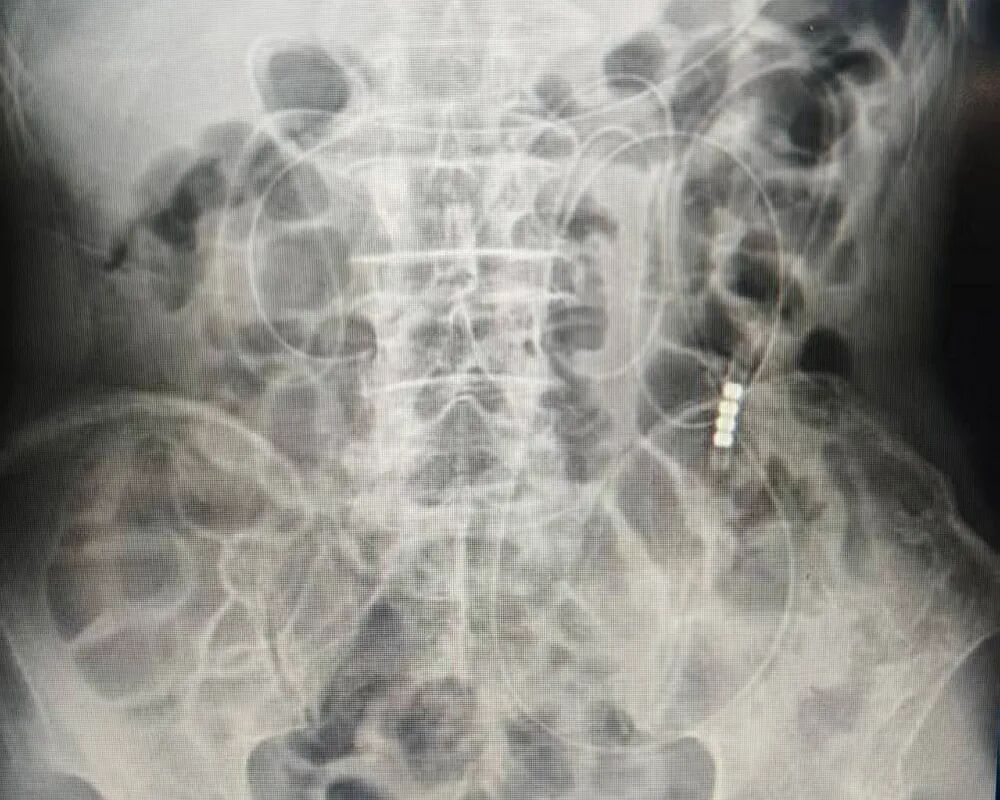

接诊后,胃肠疝外科负责人曹传培团队,结合患者病史及影像学检查,明确诊断为肠梗阻。考虑到患者高龄、有腹部手术史,开腹手术风险高、恢复慢,团队经多学科论证后,考虑采用创伤更小的“肠梗阻导管置入”微创方案。11月18日,在介入室配合下,团队为患者实施肠梗阻导管置入术,精准将导管置入深度达2.1m,手术顺利完成。